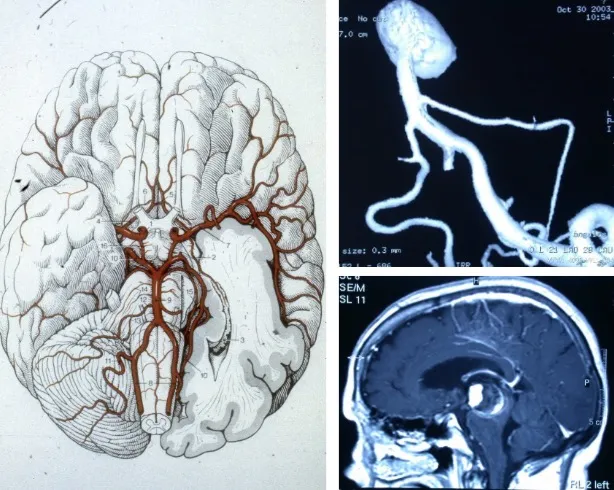

Localización de los aneurismas

Los aneurismas cerebrales se localizan preferentemente en los grandes vasos del cerebro, concretamente en las bifurcaciones arteriales. La estructura anatómica donde se concentran con mayor frecuencia es el polígono de Willis, un anillo arterial situado en la base del cerebro formado por la confluencia de las arterias principales.

En cuanto a su distribución, el 90% de los aneurismas se sitúan en la circulación anterior, que comprende las arterias carótida, cerebral anterior y cerebral media. El 10% restante se localizan en la circulación posterior (sistema vértebro-basilar), que, aunque menos frecuente, resulta más compleja de tratar desde el punto de vista médico-quirúrgico.

Los aneurismas cerebrales son dilataciones en forma de saco que se producen en las paredes arteriales, generalmente en las bifurcaciones de los grandes vasos que conforman el polígono de Willis. Se estima que hasta un 1% de la población puede albergar un aneurisma cerebral, aunque solo una proporción limitada llegará a romperse.

El punto mecánicamente más débil de una arteria es su bifurcación, el lugar donde el vaso se divide en dos ramas. En esta zona, el flujo sanguíneo impacta constantemente contra la pared antes de dividirse, sometiendo ese punto a un estrés mecánico continuo a lo largo de toda la vida.